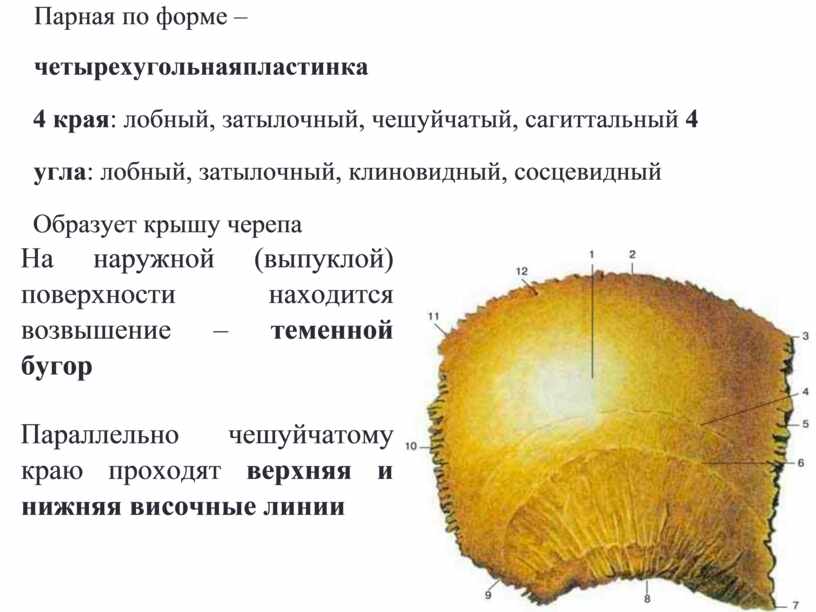

Анатомические изображения срединной сагиттальной линии черепа